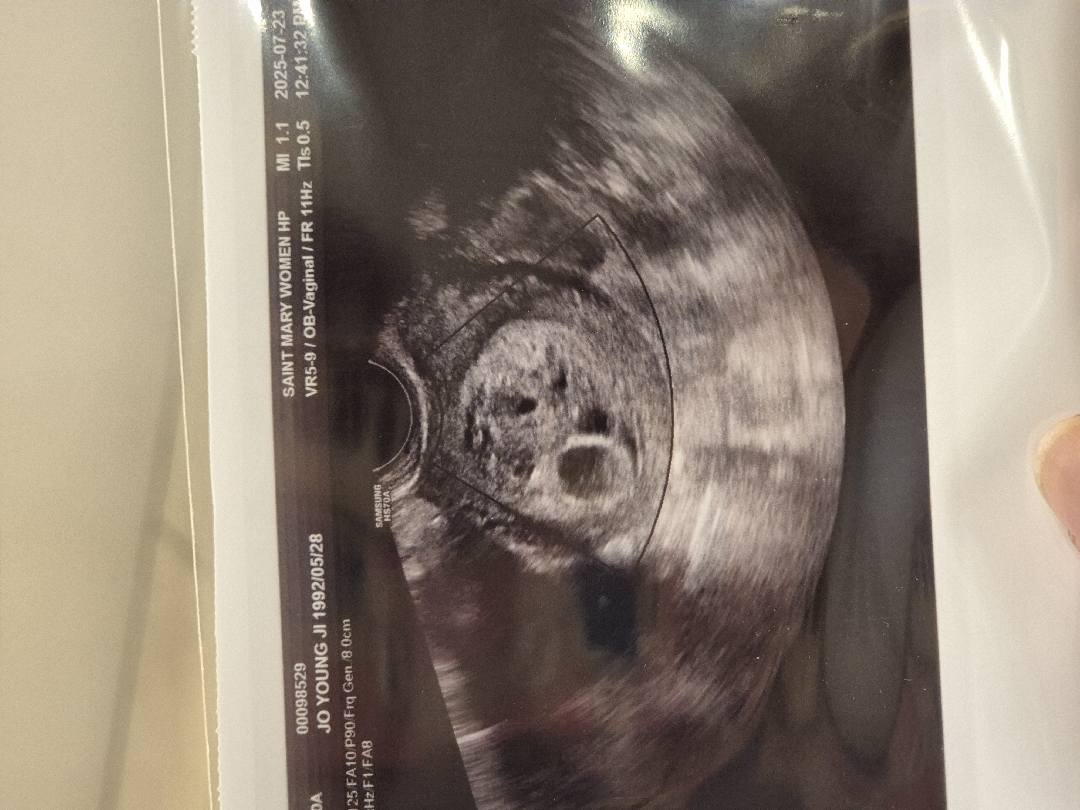

포상기태 모양이긴 한데 아기집도 있으니까 다음주에 체크해보셔야 될거같아요. 걱정하지 마세요!

막생 기준으로 5주3차에 첫 초음파를 봤어요. 아기집도 있고 난황이 보이는거 같다고 하는데 오른쪽에 포상기태 의심간다고 하더라구요 .. 다음주에 다시 초음파 보자고 하는데 제발 포상기태 아니길 바래요ㅠㅠ 보실때 포상기태 같나요???